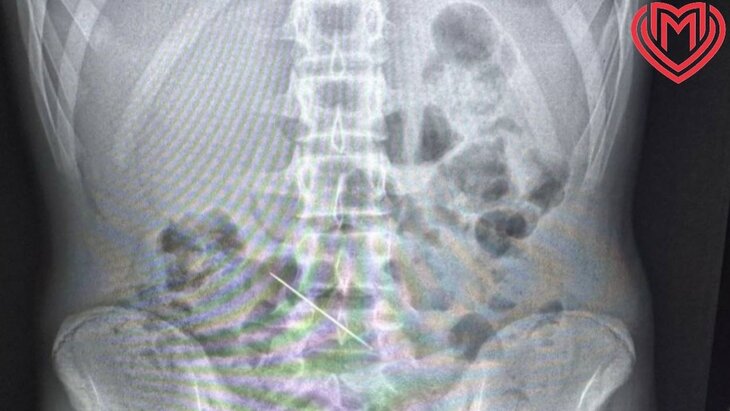

Врачи детской городской клинической больницы №9 имени Сперанского провели успешную операцию по извлечению швейной иглы из кишечника 13-летнего пациента. Об этом сообщили в пресс-службе Депздрава Москвы.

Мальчика, испытывавшего острую боль в подреберье, экстренно госпитализировали из-за подозрения на аппендицит. По итогам обследования специалисты медучреждения выяснили, что причиной дискомфорта стала 5-сантиметровая швейная игла. Инородный предмет застрял в поперечной ободочной кишке и проткнул ее.

В ходе операции по извлечению объекта врачи обнаружили небольшое отверстие размером в 2 миллиметра, располагавшееся в месте стояния иглы. Металлический предмет выступал ушком в просвет брюшной полости – брыжеечной части кишки, где более толстая стенка.